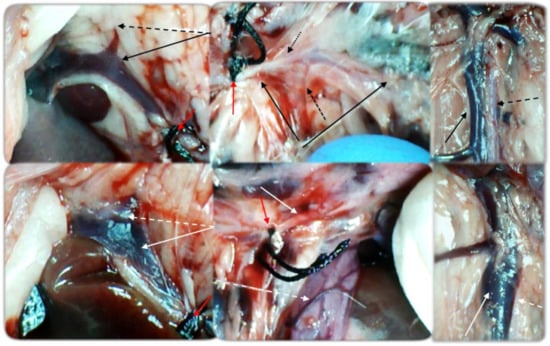

2.3. Experimental Protocol

2.7. Thrombus Assessment